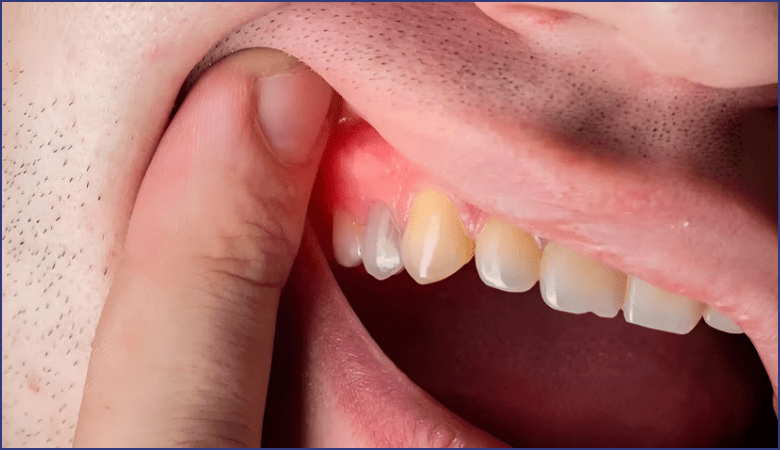

- Vùng nướu bị sưng có thể xuất hiện túi mủ, gây phồng má hoặc sưng mặt, kèm theo hiện tượng chảy máu khi chạm nhẹ.

Vùng nướu bị sưng xuất hiện túi mủ (Nguồn: Internet)